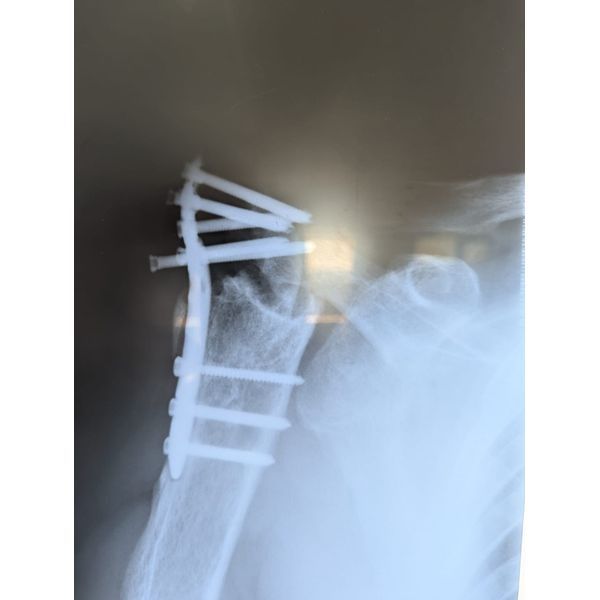

В ноябре 2021 года из-за падения пациент получил травму: закрытый перелом верхнего конца правой плечевой кости. Обратился с резкими болями и ограничением движений в области правого плечевого сустава в больницу. Во время обследований у него выявили covid-19. Приняли решение от оперативного лечения воздержаться.

Спустя время, в январе 2022 года, пациент вновь поступил в больницу, где после обследования ему выполнили операцию по остеосинтезу правой плечевой кости пластиной и винтами. Пациент начал реабилитацию, но с течением времени боль и ограничение движений возвращались. Постепенно появилась и стала нарастать деформация плечевой области. В связи с чем мужчина принял решение обратиться в ФНКЦ ФМБА России.

Несросшийся перелом проксимального отдела правой плечевой кости (ближе к плечевому суставу) в условиях МОС (металлоостеосинтеза).